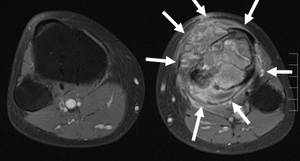

Die Diagnose erfolgt durch verschiedene Bildgebungsverfahren und bei nicht eindeutiger Situation zusätzlich durch eine geschlossene bzw. offene Probeentnahme. Das gewonnene Material wird anschließend mikroskopisch durch den Pathologen am Universitätsklinikum Ulm analysiert. Bei ausgefallenen Tumoren gibt es sog. Referenzpathologen, die deutschlandweit Zweitmeinungen abgeben, um eine optimale Diagnosestellung zu gewährleisten. Idealerweise führt die Klinik, die die Probeentnahme vorgenommen hat, auch die definitive Tumoroperation durch.

In unserer Klinik stehen folgende Verfahren zur Bildgebung zur Verfügung:

Computertomographie (CT) inklusive CT-gestützter Interventionen

Kernspintomographie (NMR / MRT)